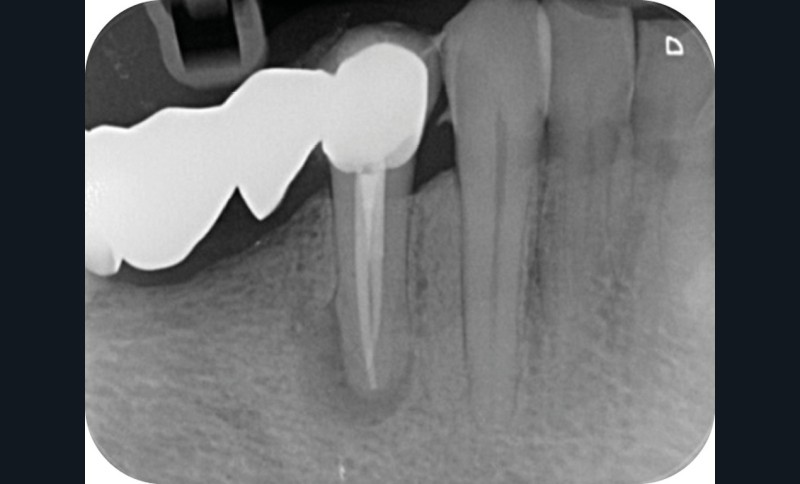

La mise en forme canalaire à travers un bridge impose des contraintes instrumentales importantes, et nécessite une analyse préopératoire minutieuse. Ici, nous avons eu recours à des limes de pré-élargissement mécanisé afin de sécuriser la trajectoire canalaire (fig. 7). Une préparation corono-apicale jusqu’à une finition apicale 25-6 % a ensuite été choisie afin d’optimiser le flux d’irrigant dans le tiers apical. À la suite de l’ajustage des maîtres cônes et d’un protocole d’irrigation finale (EDTA & NaOCl), une obturation selon la technique de condensation verticale à chaud est réalisée, puis la patiente est revue pour une restauration composite de la face occlusale (fig. 8, 9). Le contrôle à six mois révèle la disparition de la symptomatologie ainsi que des signes radiologiques de cicatrisation apicale (fig. 10).